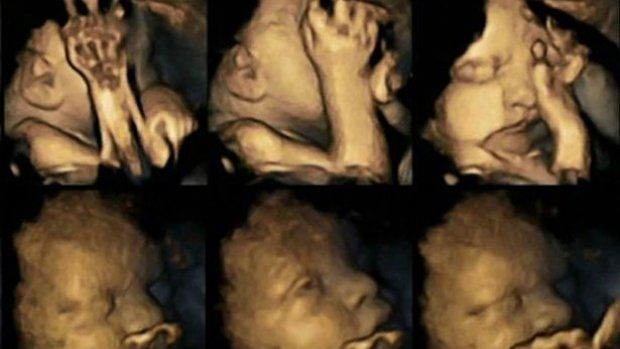

Dat roken tijdens een zwangerschap slecht is voor de ontwikkeling van het kindje, wisten we al lang. Maar nu is ook op echobeelden te zien wat het met een foetus in de baarmoeder doet als de moeder rookt.

Professor Nadja Reissland van de universiteit van Durham in Groot-Brittannië onderzocht 4D-echobeelden van 20 ongeboren kindjes. Vier van de moeders rookten tijdens de zwangerschap gemiddeld 14 sigaretten per dag, de andere moeders rookten niet. Ze bekeek echo's na 24, 28, 32 en 36 weken.

De onderzoekster keek naar de mondbewegingen van de foetus en hoe vaak het kindje het gezicht aanraakte. Naarmate de zwangerschap vorderde, bleken de foetussen van rokende vrouwen veel vaker met hun mond te bewegen en naar hun gezicht te grijpen dan die van niet-rokende moeders. Normaal gesproken neemt de beweging van een foetus juist af gedurende de zwangerschap, omdat ze meer controle krijgen over hun lichaam.

Maar de echobeelden lijken voor zich te spreken. Reissland wil de beelden gebruiken voor educatieve video's om rokende moeders over te halen te stoppen met roken.